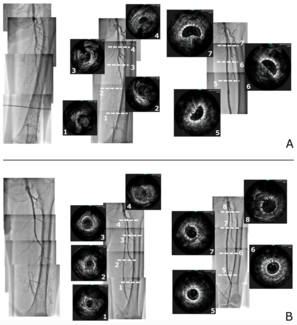

The study aim was to evaluate the impact of extravascular ultrasound-guided (EVUSG) wiring on achieving optimal vessel preparation and patency in endovascular therapy (EVT) for superficial femoral artery (SFA) chronic total occlusion (CTO).